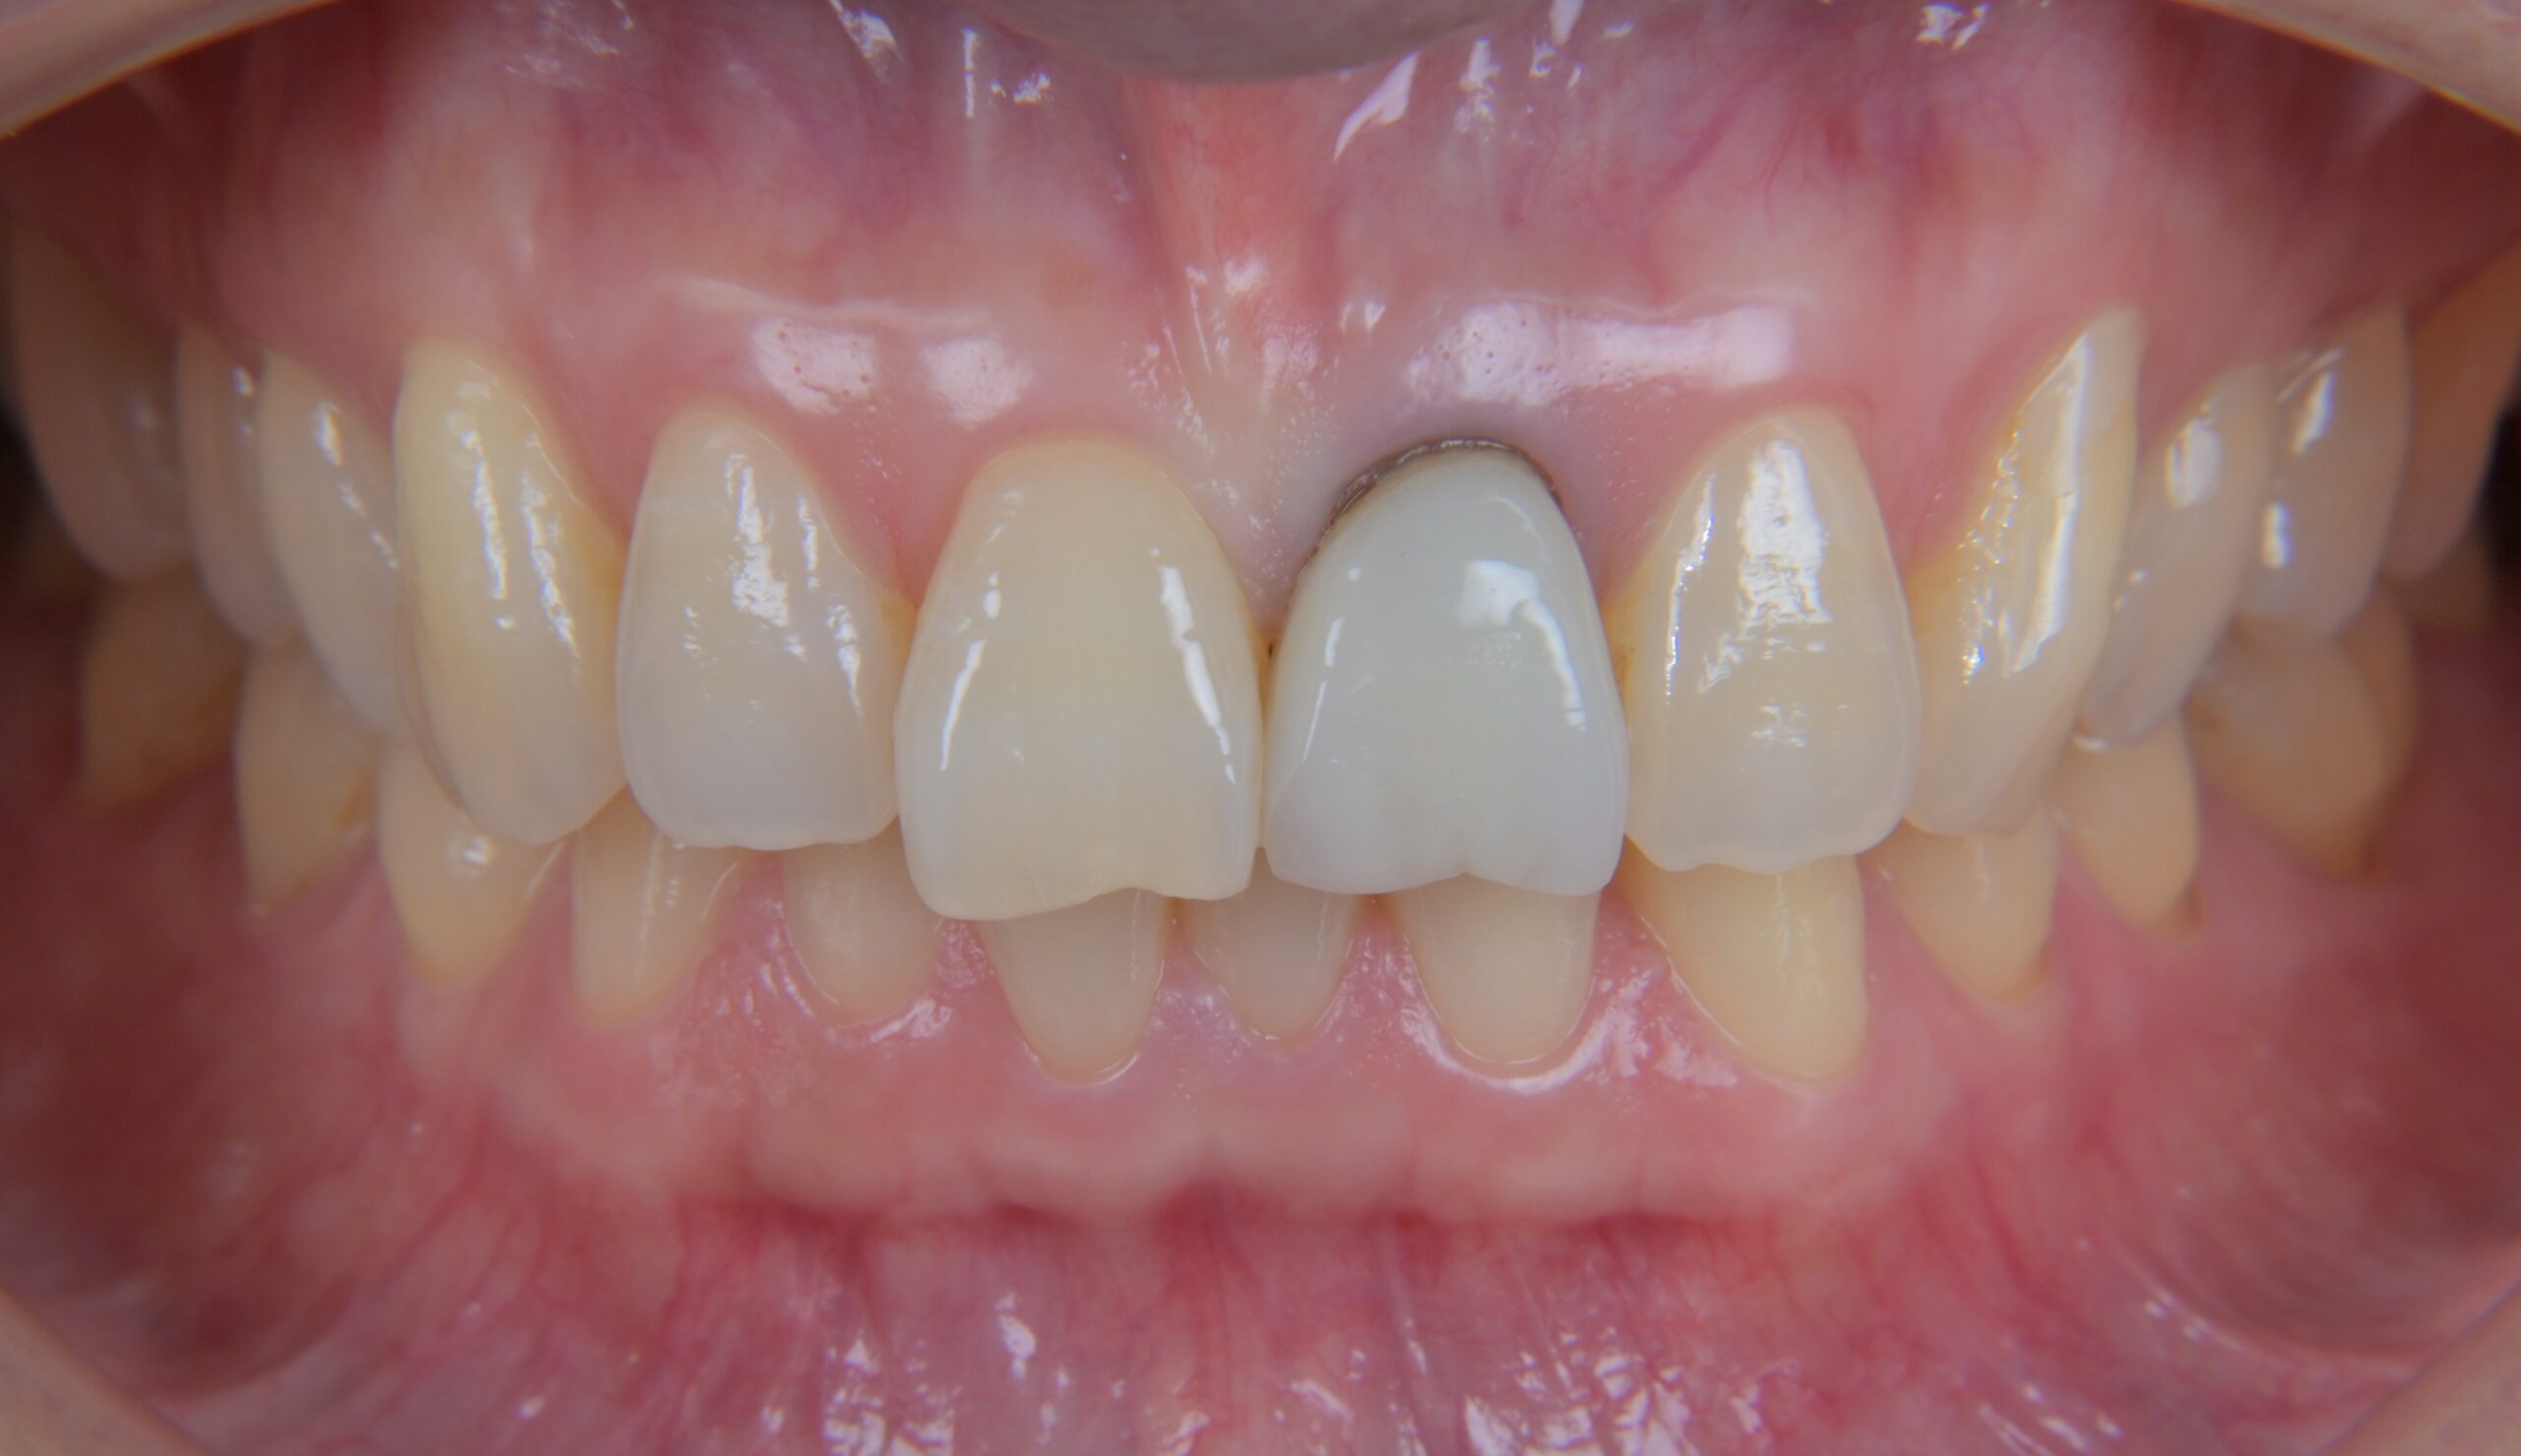

前歯のジルコニアクラウン症例

Before

After

治療内容

左上1番の被せ物に色の違いや、段差があるのが気になる為やり変えを希望されました。

古い被せ物を除去し、1回目の仮歯に置き換えます。

患者様と相談し形態を修正し、2回目の仮歯に移行します。

その後、最終的な被せ物を作るための型取りを行います。

最終的にジルコニアクラウンにて被せ物を接着しました。

担当歯科医師:平沼 佳朗